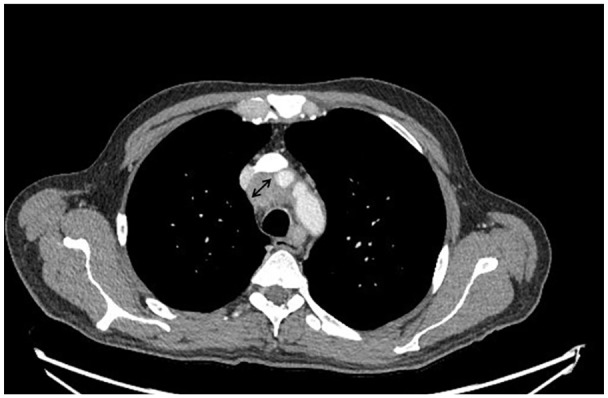

Recurrent deep vein thrombosis (DVT) is a common complication, particularly in cancer patients. We present a case of a 50-year-old male with a history of a previous DVT. Despite therapeutic anticoagulation with apixaban, the patient developed recurrent DVT involving the common femoral, popliteal, and foreleg veins. He was started on a heparin drip in the hospital, but despite this, his DVT worsened. Imaging studies revealed mediastinal and hilar lymphadenopathy, raising suspicion of malignancy. The workup revealed elevated tumor markers, while the thrombophilia panel was unremarkable. Despite aggressive management, including mechanical thrombectomy, catheter-directed thrombolysis, and the placement of an inferior vena cava filter, the patient's condition continued to deteriorate. A biopsy of the mediastinal lymph nodes revealed poorly differentiated mucinous adenocarcinoma with molecular analysis consistent with hepatobiliary origin, and the patient was diagnosed with stage IVB gallbladder cancer. Given the rarity of gallbladder cancer and its association with hypercoagulability, this case highlights the importance of considering cancer as an underlying cause of recurrent DVT after ruling out common causes. Early recognition and a comprehensive diagnostic approach are essential for managing such cases. The patient was started on chemotherapy while maintaining anticoagulation for recurrent DVT.